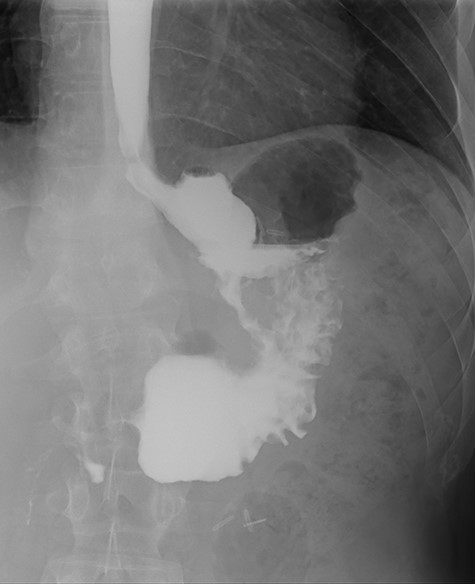

Three months after endoscopic treatment, the patient started complaining of epigastric pain again, without other gastrointestinal symptoms or weight regain. An upper gastrointestinal (GI) contrast swallow study showed recurrence of the GGF and GJA stenosis (see Fig. 4).

Upper gastrointestinal contrast swallow study image where it is possible to see a gastro-gastric fistula with opacification of the excluded stomach.